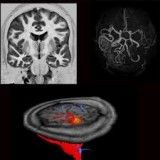

Se quer saber como sair da depressão no Itaim Bibi, entre em contato com a OHR Psiquiatria, onde você terá boas chances de total recuperação da depressão. Disponibilizamos uma série de tratamentos que podem ser usados de forma combinada. A saber: medicamentos convencionais, psicoterapia e infusões de doses baixas de cetamina.